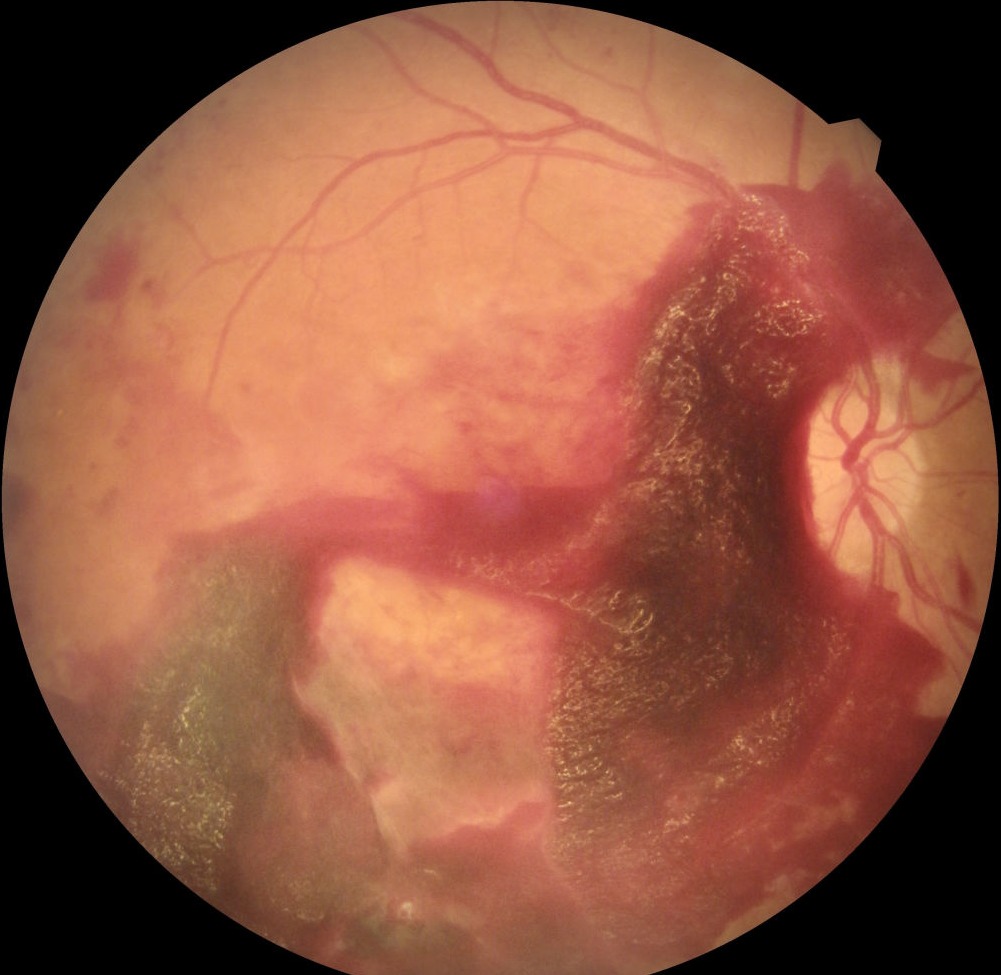

Retinada diyabete bağlı yaygın ve şiddetli kanamalar

Diyabetik retinopati gözün en iç katmanını oluşturan ve görmeyi sağlayan “retina” tabakasında oluşan hasarı ifade eder. Retinayı besleyen damarlarda oluşan tıkanıklıklar, damar geçirgenliğinin artmasına, retinanın beslenmesinin bozulmasına ve görme kaybına neden olur. Diyabetik retinopatinin erken dönemlerinde sıklıkla görmede belirgin kayıp olmaksızın retina muayenesinde kolaylıkla tespit edilen kanama ve sızıntılar mevcuttur. İlerleyen dönemde retinanın beslenmesinin daha da bozulması sağlıksız yeni damarların oluşmasına ve bu damarlardan gözün içine tekrarlayan kanamalara neden olur. Daha ileri aşamalarda retinanın yapısı ve ışık hassasiyeti kalıcı olarak bozulur ve görme kaybı oluşur.

Diyabetik retinopati tedavisinde amaç; retina hasarının yavaşlatılması ve görmenin korunmasıdır. Bunun için sıklıkla uygulanan tedaviler oluşan hasarın durumuna göre değişen sıklıkta tekrarlanan göz içi enjeksiyonları ve retinaya lazer uygulamasıdır. Tekrarlayan çok şiddetli göz içi kanamalarında ve retinanın gelişen anormal damarlar nedeniyle büzüşerek ayrılması durumunda "retina dekolmanı" geliştiğinde “vitrektomi” ameliyatı ile kanama temizlenir ve retina tamiri yapılır.